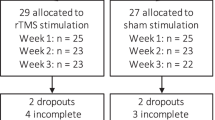

In phase 2, based on a previous study [45], non-invasive rTMS (Magstim Inc., Wales, UK) was performed, using double-cone coil, as a prognostic test. rTMS consisted of active stimulation at 1 Hz with 50% machine output in tonic mode for 5 consecutive days and placebo for 5 consecutive days in random order. For placebo rTMS, the coil was placed perpendicular to the scalp and was applied at the same frequency and intensity as active rTMS to ensure that the participants were exposed to the same clicking noise. Daily craving before rTMS session was assessed on a scale of 1 (not at all) to 10 (the most ever) to the question: “Please rate how strong your alcohol craving is right now by circling a number on the 10-point scale”. All participants (n = 9) enrolled in the study demonstrated ≥ 50% reduction in alcohol craving self-ratings to active rTMS stimulation and were considered eligible to continue to the next phase [45]. One participant declined to have the implant. At the end of the tenth session, all participants were able to identify the placebo and active rTMS sessions. However, from a clinical perspective, the participants’ speculation of order of stimulation did not seem to affect the therapeutic effect of active stimulation. This is evident from Table 3 that, among those who were implanted with the electrode (n = 8), there was a decrease in craving during the first 5 consecutive sessions in group 1 (active followed by placebo) compared to group 2 (placebo followed by active) (Table 3).

In phase 4, the electrodes were activated using an internal pulse generator (IPG) post-surgery. The original study design included a randomised immediate (3 days post-surgery) or delayed (17 days post-surgery) start protocol for activation of electrodes. However, due to adverse events, the original randomised study design was deemed unfeasible by the research team in consultation with the Data Safety Monitoring Board after the fourth implant. Time points of IPG activation and deactivation post-surgery as well as adverse events for each participant are presented in Table 4. By 2 months post-implant, all electrodes were activated.